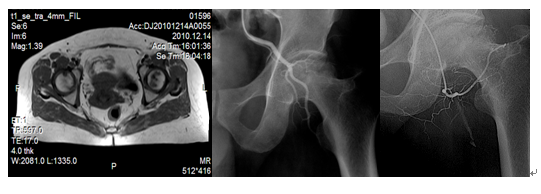

股骨头坏死又称股骨头缺血性坏死,病因复杂,是因各种原因导致股骨头供血不足,营养缺乏而致骨质破坏,治疗困难,最终导致关节畸形!微创介入治疗通过局部溶栓和扩张血管结合中药治疗以改善股骨头血供,从而解决股骨头营养,促进股骨头修复,对0--II期病变效果尤为显著,对III-IV期病变也有很好的止痛效果,结合活血化淤中药治疗,疗效独特!

典型病例:女、63岁,2010年10月在我院MR检查发现双侧股骨头缺血性坏死II期,行三次介入术后。2014年复查提示病变基本愈合。